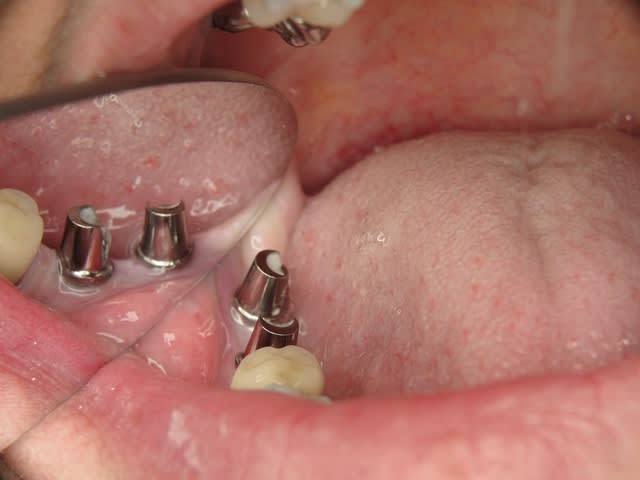

Maintenant concernant la demande de scans : je poste ce cas, une patiente vient me voir avec son scan car elle a consulté d'autres "spécialistes" et on lui refuse la pose d'implant secteur 4 où alors avec greffe préalable..Ca se discute..pas de temps à perdre je sais faire autrement..

Avec la chir trans gingivale technique MIMI ( Oui..un post sur la technique bientôt ..) j'ai pu placer deux 3,5/8mm..aurai je eu le meme résultat avec un lambeau..j'en doute..Les couronnes sont en titane. Recul clinique 2 ans ras. Simple efficace rapide moins onéreux satisfaisant pour le praticien et la patiente..